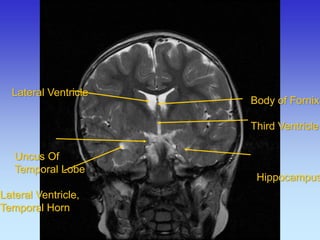

Lateral Ventricle Uncus Of Temporal Lobe Lateral Ventricle, Temporal Horn

Body of Fornix

Third Ventricle

Hippocampus